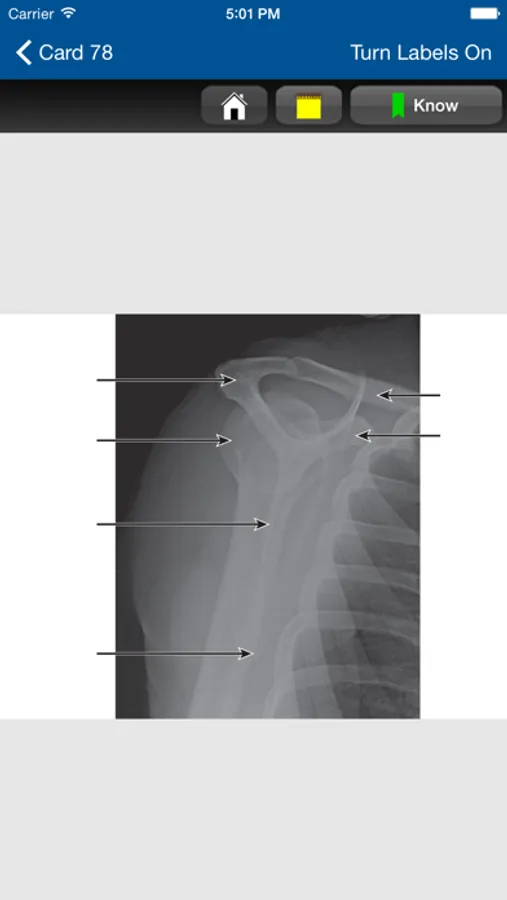

• Each card includes a high-quality photograph of correct patient positioning with details of the projection and the corresponding X-ray, technical information, and image evaluation criteria

• Most cards include a high-resolution radiographic image and photographs demonstrating each position/projection

This app is very intuitive and easy to navigate, allowing you to browse the contents or search for topics. The powerful search tool gives you word suggestions that appear in the text as you type, so it is lightning fast and helps with spelling those long medical terms. The search tool also keeps a recent history of past search terms so you can go back to a previous search result very easily. You can also add notes to each flashcard, as well as bookmark flashcards as Know and Don't Know to help with studying. Many of the flashcards also have images that have labels you can turn on and off to aid with studying. You can also change the text size for easier reading.